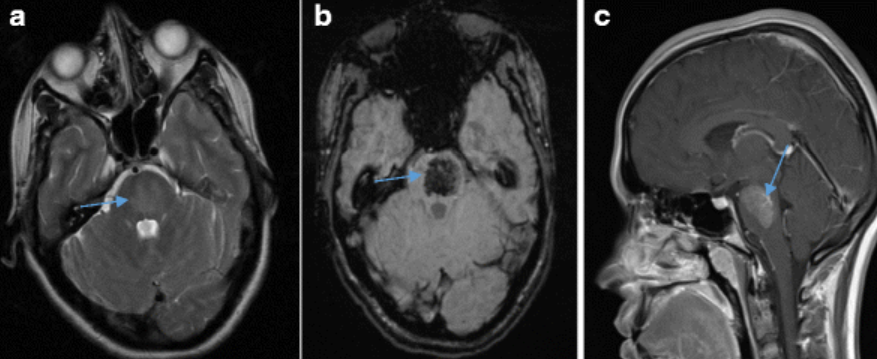

脑干较大毛细血管扩张症,T2WI 呈高信号,SWI 呈低信号,增强呈片状稍淡强化,可见引流静脉

右侧尾状核头毛细血管扩张症,平扫看不到,增强呈结节样强化,无水肿,矢状位和冠状位仔细观察结节内可见静脉向室管膜下引流